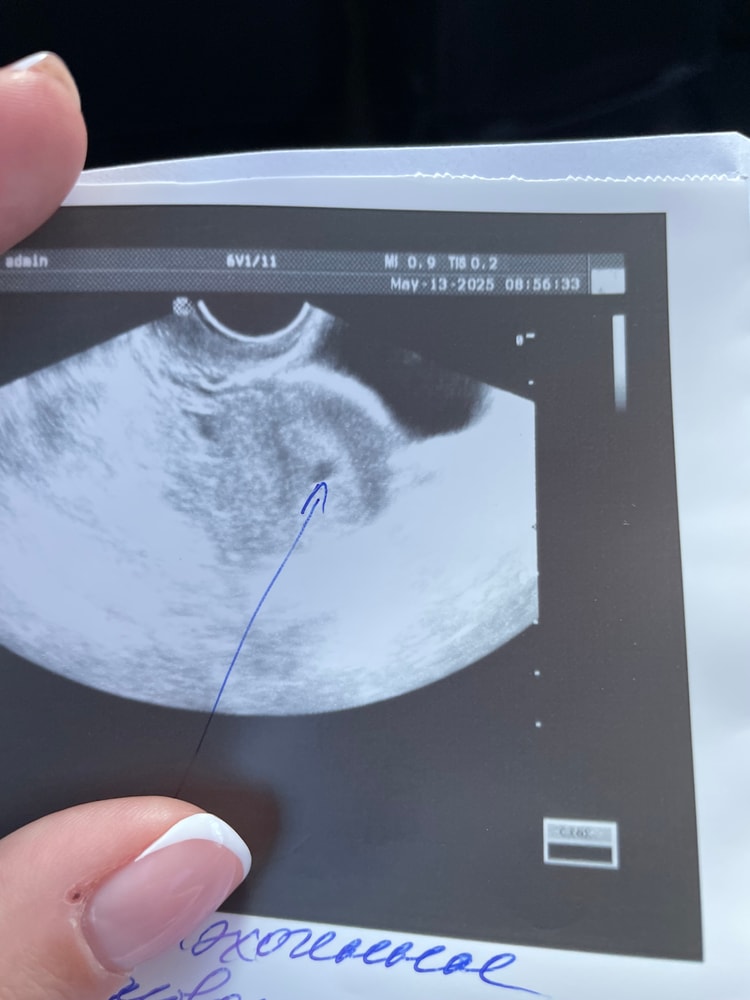

В матке что-то похожее на плодное яйцо ,но тест пустой

Всем привет 🫶овуляцию не поймала ,делала тесты каждый день . На 29 ДЦ пошла на фолликулометрию и узист говорит «вижу в матке образование похожее на плодное яйцо» я обалдела , ЖТ нет , в яичнике фолликул 14 мм самый большой , сделала феми тест,он нарисовал тень ,мама чек пустой .

дополняю спустя время. Никакой беременности конечно нет

более грамотный узист объяснила что это эндометрий который уже начал отторгаться потому что скоро месячные 😅

срез сосуда, полип эндометрия, складка эндометрия.

на 29дц ну никак не видно плодное яйцо при всем желании.

Чтобы его там увидеть, хгч должно быть 1000+

А это обычно уже дней 5 задержки и полоски на тестах жирные.